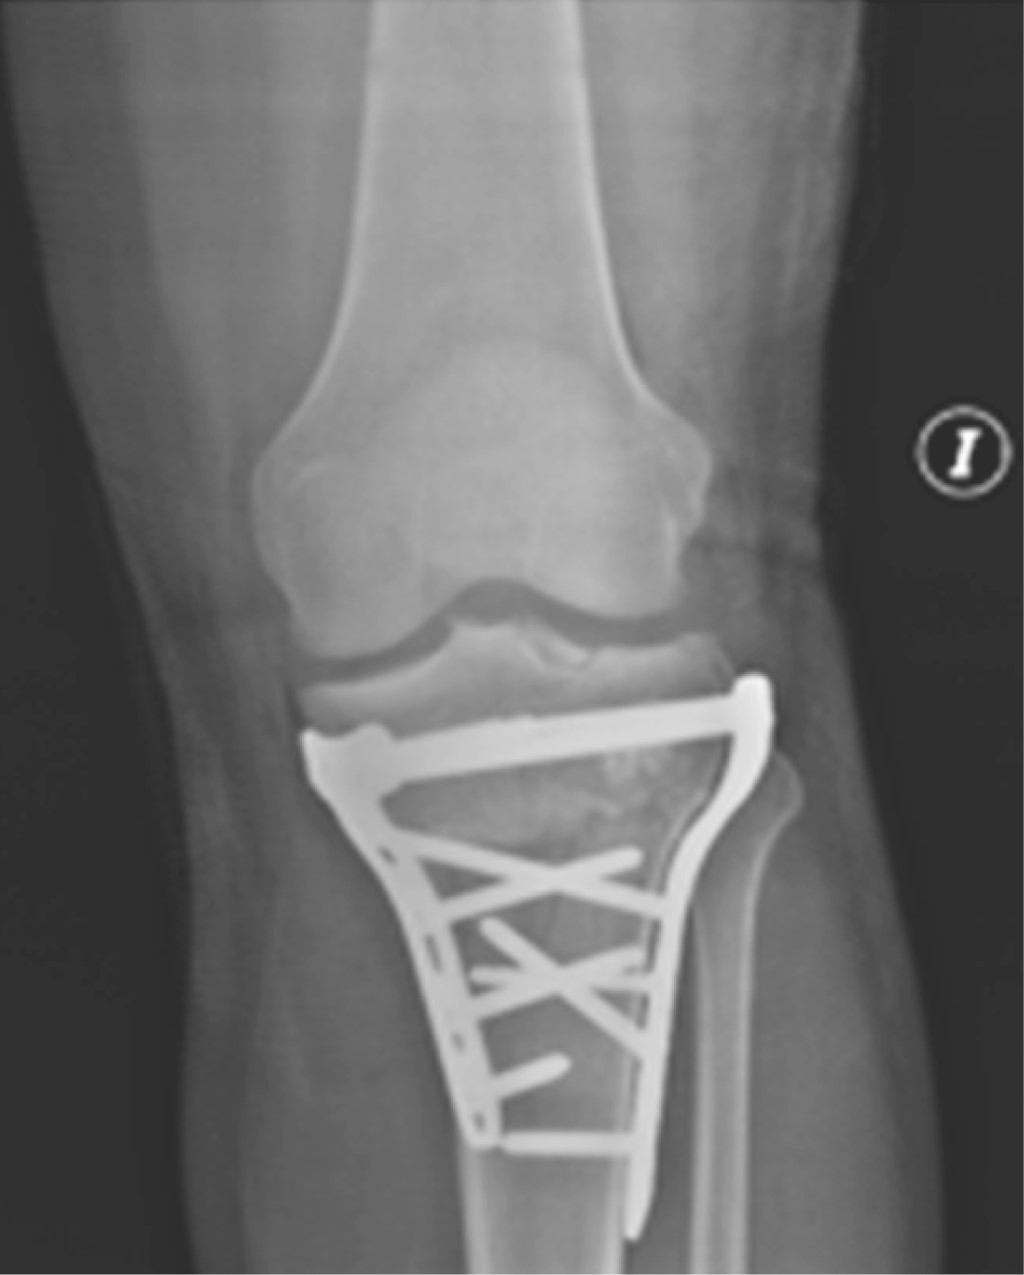

Se le practica osteosíntesis de fémur con clavo cefalomedular largo a foco cerrado corrigiendo la fractura subtrocanteriana y se le aplica tutor externo transarticular de rodilla como medida de control de daño local provisional; 15 días después se realiza osteosíntesis definitiva de su fractura de platillos tibiales. Evolución adecuada y satisfactoria de platillos tibiales (Figura 2).

El paciente evolucionó adecuadamente, la herida quirúrgica cicatrizó por completo hasta el día de hoy con infección en remisión y evidencia radiológica de consolidación de la fractura, además paciente asintomático con función preservada de la extremidad (Figuras 7 y 8).

Figura 2

Figura 8